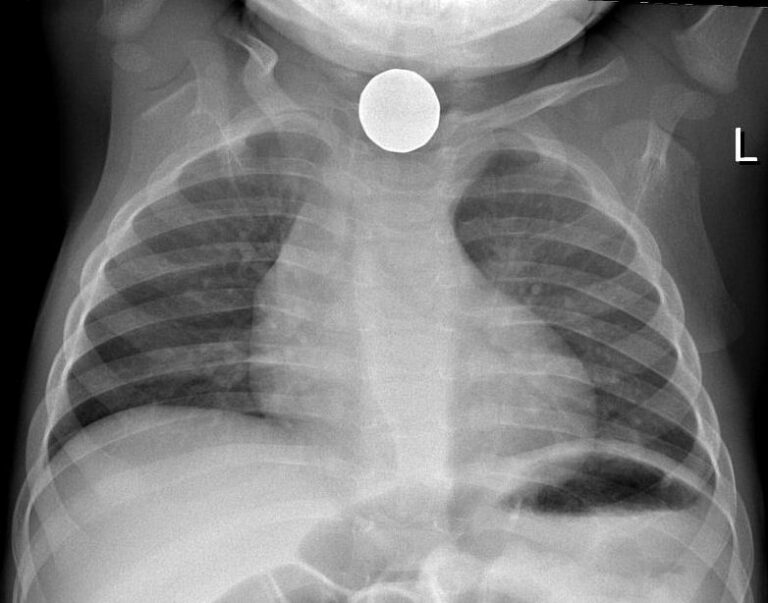

From openpress.usask.ca

Foreign Body Ingestion/Aspiration Undergraduate Diagnostic Imaging Aspirated Foreign Body Foreign body aspiration is the fourth leading cause of death in preschool. Foreign body aspiration is when an object is inhaled and becomes lodged in a child’s airway or lungs. Symptoms include sudden onset of respiratory distress associated. Inhalation of a foreign body into the larynx and respiratory tract. An aspirated solid or semisolid object may lodge in the larynx. Aspirated Foreign Body.

From radiopaedia.org

Foreign body in airway Image Aspirated Foreign Body It's natural for children to explore their environment by seeing, touching and tasting. Symptoms include sudden onset of respiratory distress associated. Foreign body aspiration is the fourth leading cause of death in preschool. Foreign body aspiration is when an object is inhaled and becomes lodged in a child’s airway or lungs. Inhalation of a foreign body into the larynx and. Aspirated Foreign Body.